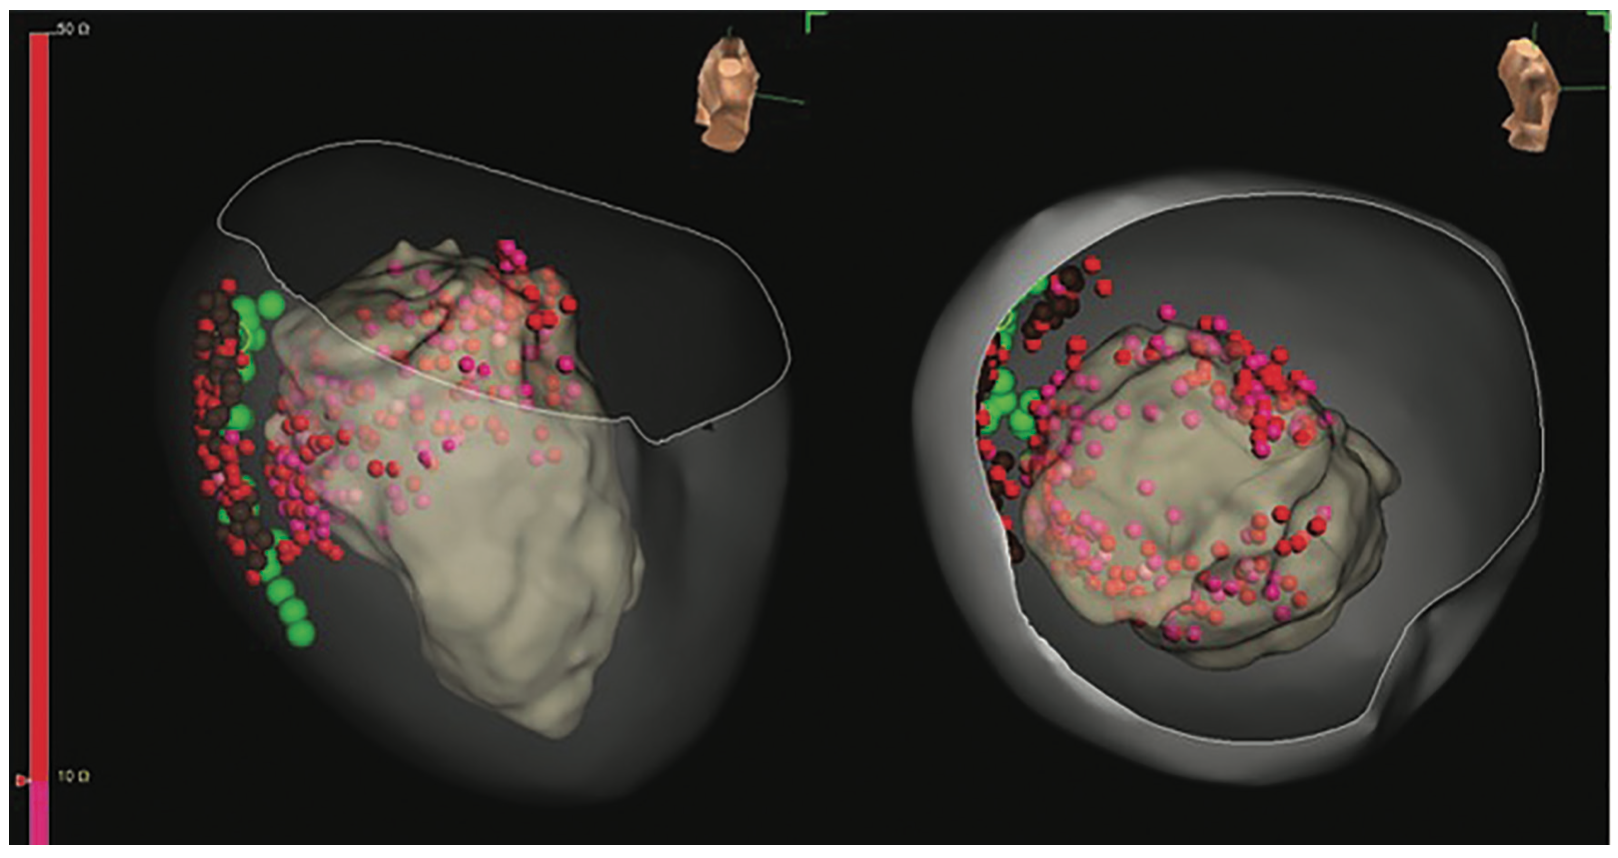

Conscious sedation was administered by the anesthesia team to lower the risk of hemodynamic compromise, which can be seen with general anesthesia. Because preop imaging suggested an epicardial substrate for VT, the patient’s chest was prepped in a sterile manner to facilitate possible epicardial access. An intracardiac echocardiography (ICE) catheter was inserted in the right atrium and ventricle. Ultrasound imaging of the LV showed basal inferolateral wall thinning with enhanced echogenicity of the epicardium, suggesting possible scar. Subsequent mapping of the LV was performed using a multipolar mapping catheter through a steerable sheath after a single transseptal puncture. A target activated clotting time (ACT) of 300-350 seconds was achieved with heparin boluses and a continuous infusion. To facilitate electroanatomic mapping, pacing was performed from the right ventricle using a quadripolar catheter. Using this approach, a detailed isochronal late activation and bipolar voltage map was created, confirming a predominantly basal inferolateral low voltage with areas of isochronal crowding (Figure 3). The patient was pretreated with intravenous (IV) norepinephrine (.03 mcg/kg/min) infusion in case of hypotension and programmed ventricular stimulation was performed. This induced several different right bundle branch block (RBBB) morphology monomorphic VTs with cycle lengths varying from 280-330 milliseconds, with positive precordial concordance suggestive of a basal LV origin requiring external cardioversion. However, none of the induced VTs had matching ICD electrograms to the clinical VT. As such, the decision was made to proceed with a substrate-based approach targeting endocardial substrate corresponding with regions with isochronal crowding and late potentials within the bipolar scar. A half-normal saline irrigated ablation catheter was introduced and ablation was performed (30-40 watts, duration of 60-300 seconds) with contact force >10g in the low-voltage basal LV segments (Figure 4).

The isochronal late activation map was repeated in the epicardium, identifying isochronal crowding in the basal inferolateral LV epicardium corresponding to the endocardial site (Figure 5). Coronary angiography confirmed a distance (>5 mm) of the left circumflex artery and its branches from the region of interest (Figure 6), and the phrenic nerve position was confirmed with high-output pacing and marked on the electroanatomic map. Extensive substrate-based ablation of the region of interest followed while avoiding the phrenic nerve. Irrigation of the catheter during epicardial ablation was lowered to 5 mL/min and the steerable sheath was aspirated regularly to maintain a dry pericardial space. After this, programmed stimulation was repeated and 2 more RBBB-morphology monomorphic VTs were induced. Pace mapping identified a more anterolateral epicardial origin and further ablation was performed in this area (Figure 7). The procedure was then concluded, the pericardium aspirated dry, and the epicardial sheath was replaced with a pigtail drain to be left in site overnight. ICE revealed no residual epicardial effusion, and 20 mL of 1% bupivacaine and 200 mg of triamcinolone were injected in the pericardial space for postprocedural analgesia and anti-inflammatory effect. All venous sheaths were removed and hemostasis was achieved using a closure device. IV heparin was continued for systemic anticoagulation given extensive endocardial LV ablation. There was no further drainage from the pericardial drain, which was pulled shortly thereafter, and colchicine was given for 2 weeks postablation.